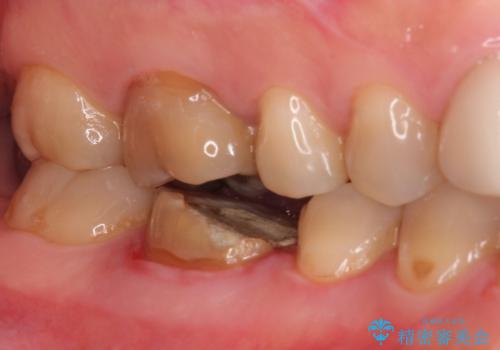

根管内を見てみると、近心根は本来の根管とは違うところを削られて髄床底でパーフォレーションを起こしていました。

また、遠心根でも本来の根管とは逸脱した方向に根管形成されていましたが、修正し充填を行っています。

パーフォレーション部位に関しては、口腔内との交通がなければMTAセメントを用いて修復することで、高い予知性を期待できます。